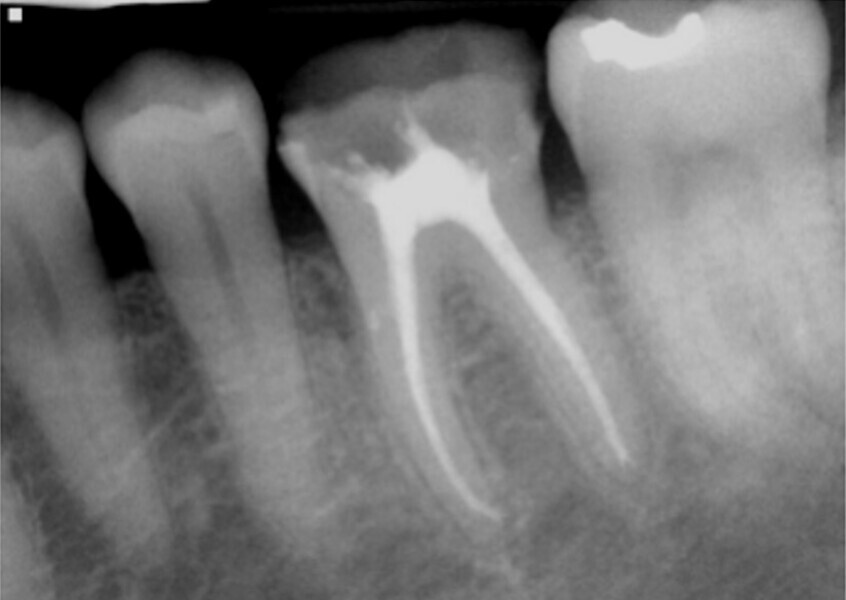

Fig. 4: Orifice-directed access in a molar utilizing Endoguide burs to conserve tooth structure while giving straight line access into the canals.